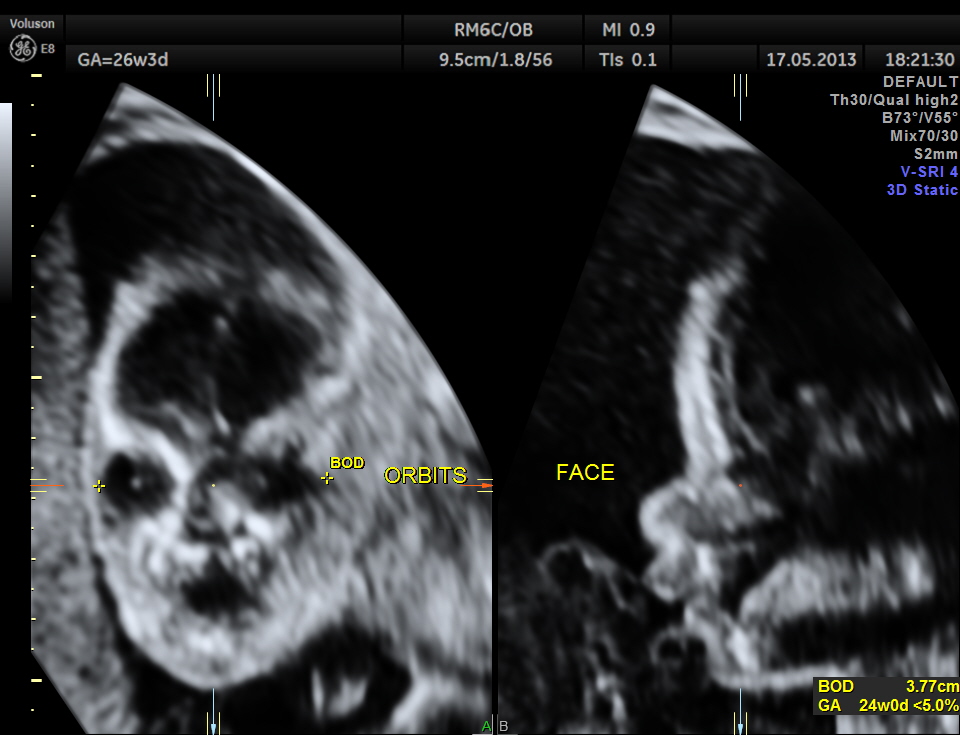

Cerebellum appears relatively smaller and corresponds to a GA of 22 to 23 weeks. Usually the cerebellum corresponds very closely to the GA and would be very useful to follow in cases of IUGR.

The following images show the face and the palate.

This fetus did not show any oro-facial clefts ; heart and spine appeared normal.

Cerebellum was < 2.3 %tile , suggestive of possible cerebellar hypoplasia. Unfortunately this patient was lost for follow up .